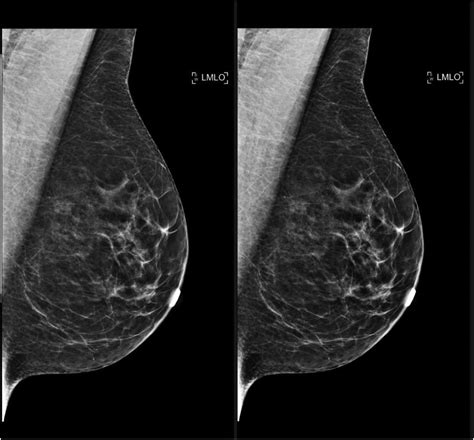

One of the most important factors influencing the appearance of your scan is breast density. Dense breast tissue contains more fibrous and glandular tissue compared to fatty tissue. On a mammogram, fatty tissue appears dark and transparent, while dense tissue appears white and opaque. This is why understanding density is vital when viewing normal mammogram images:

- Fatty Breasts: These are easier to read because masses stand out clearly against the dark background.

- Scattered Fibroglandular Densities: This is a very common classification where most of the tissue is fatty but with some scattered areas of density.

- Heterogeneously Dense: This tissue can make it harder to see small masses, as the white density can "mask" potential concerns.

- Extremely Dense: This classification presents the highest challenge for standard imaging, sometimes requiring additional screening like ultrasound or MRI.